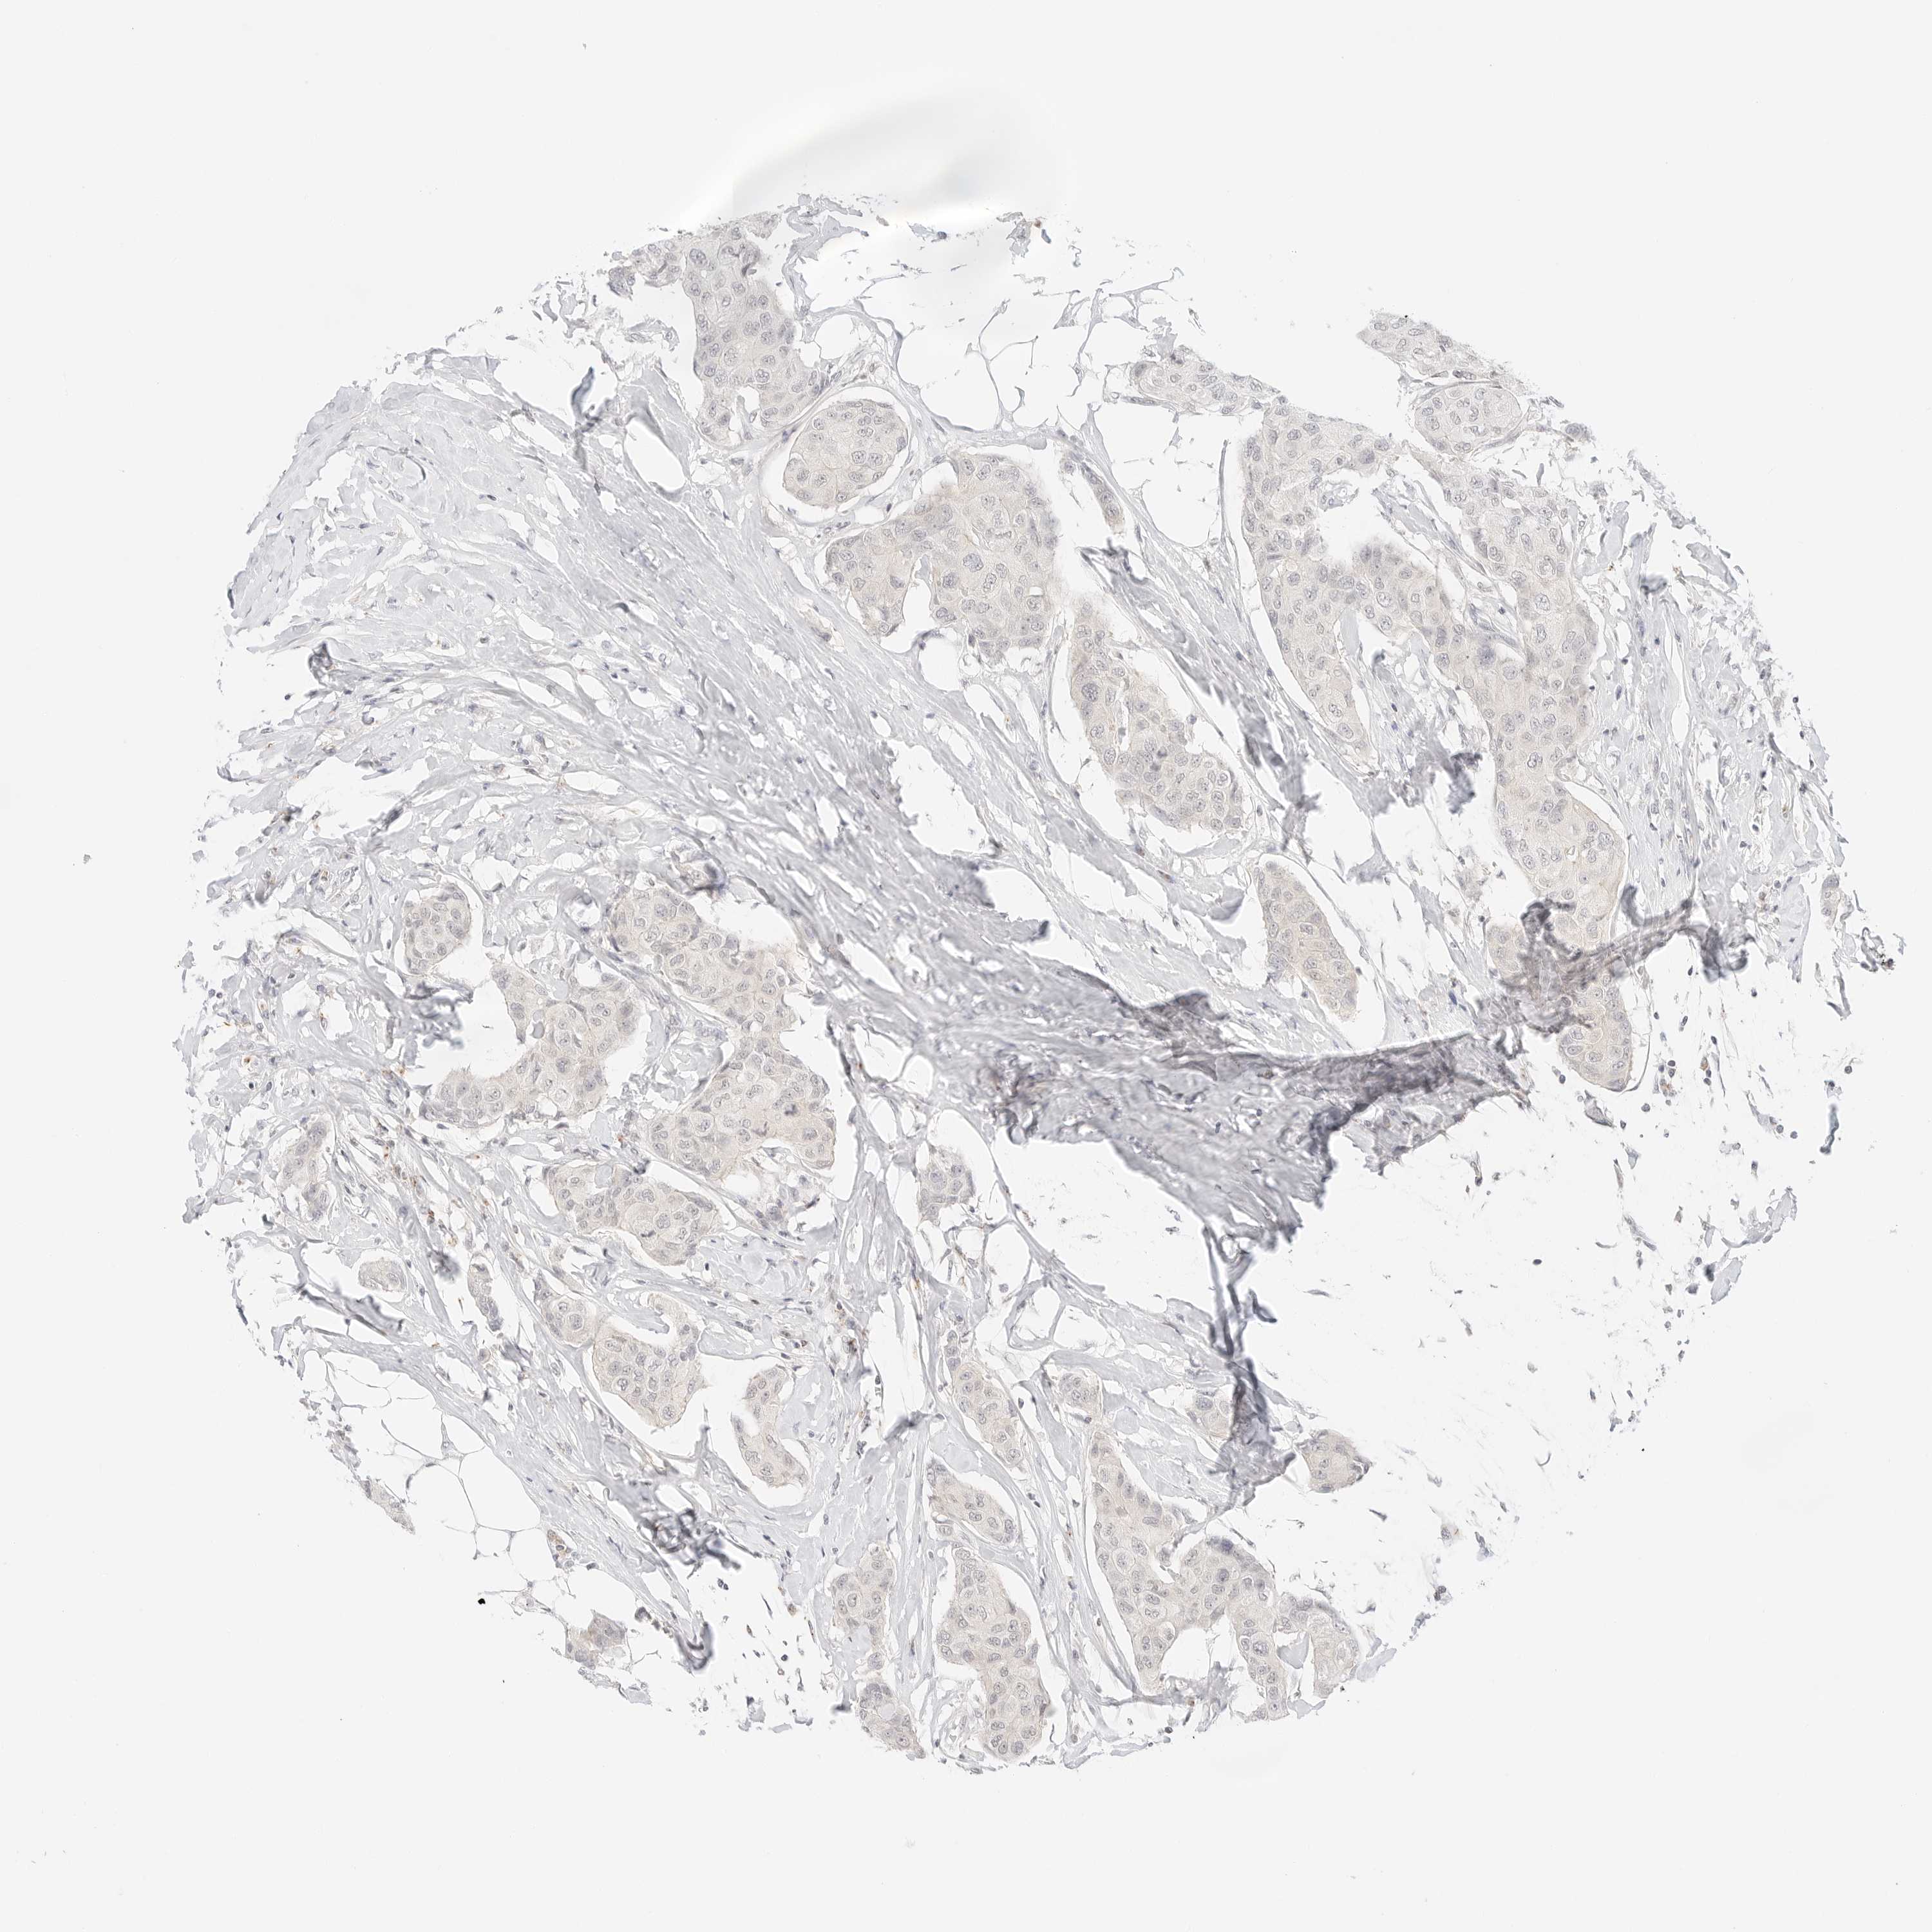

CANCER BREAST CANCER Show tissue menu

Breast cancer

Human cancer